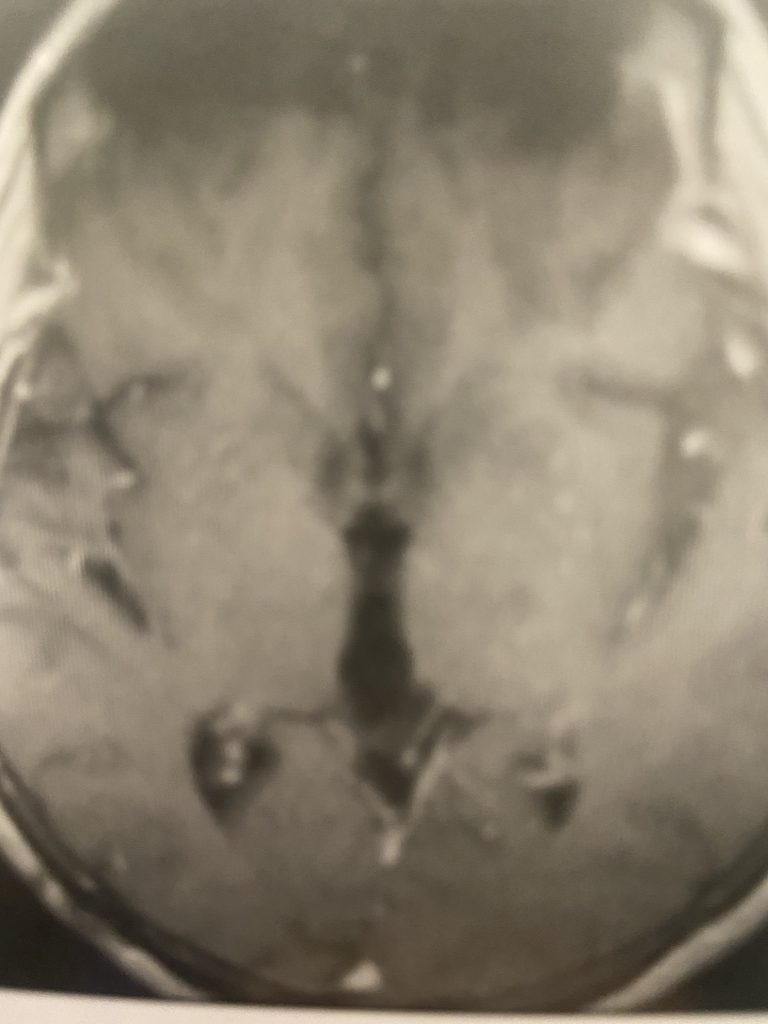

Figure 4

Postoperative post contrast axial MRIs demonstrating complete removal of the tumor with resolution of the hydrocephalus.

Subsequently, the hydrocephalus resolved and the patient did not require shunting. Her pre-operative symptoms all resolved. Follow up MRI demonstrated complete removal of the tumor.